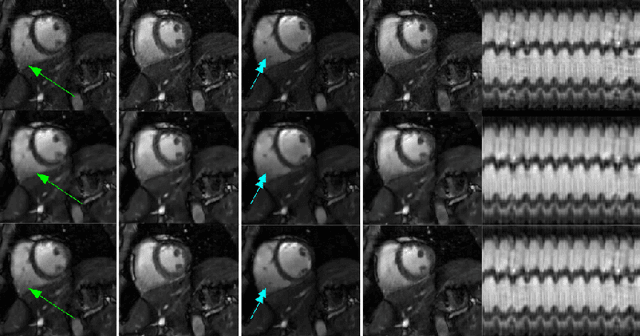

Abstract:We introduce a two step algorithm with theoretical guarantees to recover a jointly sparse and low-rank matrix from undersampled measurements of its columns. The algorithm first estimates the row subspace of the matrix using a set of common measurements of the columns. In the second step, the subspace aware recovery of the matrix is solved using a simple least square algorithm. The results are verified in the context of recovering CINE data from undersampled measurements; we obtain good recovery when the sampling conditions are satisfied.

Abstract:We consider the recovery of a low rank and jointly sparse matrix from under sampled measurements of its columns. This problem is highly relevant in the recovery of dynamic MRI data with high spatio-temporal resolution, where each column of the matrix corresponds to a frame in the image time series; the matrix is highly low-rank since the frames are highly correlated. Similarly the non-zero locations of the matrix in appropriate transform/frame domains (e.g. wavelet, gradient) are roughly the same in different frame. The superset of the support can be safely assumed to be jointly sparse. Unlike the classical multiple measurement vector (MMV) setup that measures all the snapshots using the same matrix, we consider each snapshot to be measured using a different measurement matrix. We show that this approach reduces the total number of measurements, especially when the rank of the matrix is much smaller than than its sparsity. Our experiments in the context of dynamic imaging shows that this approach is very useful in realizing free breathing cardiac MRI.